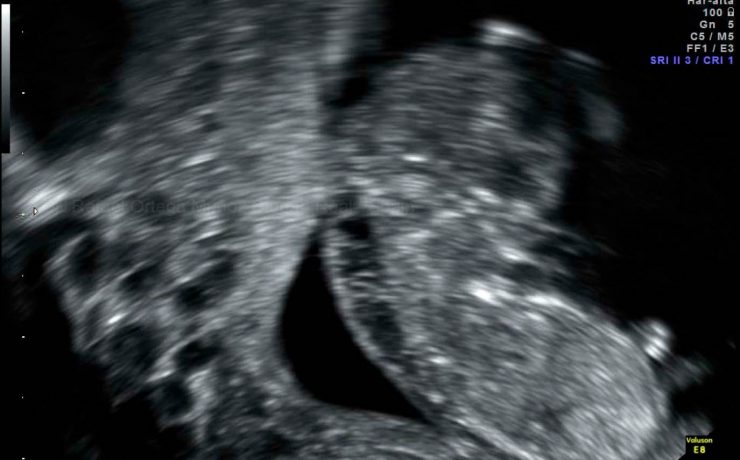

Caso clínico Se presenta un caso clínico de hematocervix diagnosticado por ultrasonografía en una paciente peri menopáusica sin antecedentes de patología cervical. Se discuten las causas de esta alteración, la utilidad del diagnóstico por ultrasonido, su tratamiento quirúrgico y su relación con patologías en otros órganos y sistemas. Introducción La